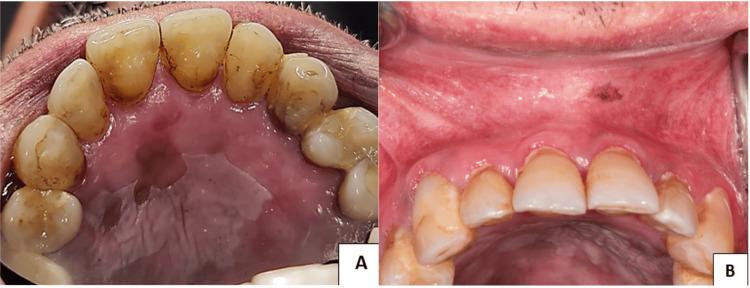

Hematopoietic stem cell transplantation is the only curative intervention for myelodysplastic syndrome, with graft-versus-host disease (GVHD) being a frequently encountered consequence. GVHD is classified as acute (aGVHD) or chronic (cGVHD). The oral cavity is the most impacted by chronic. Oral manifestations of cGVHD are variable and include plaque, Wickham striae, and lichenoid patches. In order to prevent malignant misdiagnosis, the 2014 NIH consensus report decided to exclude white plaque as a diagnostic indicator for oral cGVHD. Nevertheless, it is still possible to classify a white plaque lesion as cGVHD through histological confirmation. The performance of a biopsy should be undertaken following meticulous consideration and a thorough evaluation of the associated risks and benefits. The in-depth review of oral cancer risk assessment is crucial, necessitating a careful review of multiple factors to accurately estimate the likelihood of malignant transformation in individuals with oral cGVHD. This report describes a case of oral cGVHD manifesting as hyperkeratotic plaque lesions confirmed by histopathology in a 62-year-old man who received an allogeneic hematopoietic stem cell transplant over a decade ago.

造血干细胞移植是骨髓增生异常综合征唯一的治愈性干预措施,移植物抗宿主病(GVHD)是其常见的后果。GVHD分为急性(aGVHD)或慢性(cGVHD)。口腔是受慢性GVHD影响最严重的部位。cGVHD的口腔表现多样,包括斑块、威克姆纹和苔藓样斑片。为防止恶性误诊,2014年美国国立卫生研究院(NIH)共识报告决定将白色斑块排除在口腔cGVHD的诊断指标之外。然而,通过组织学确认仍有可能将白色斑块病变归类为cGVHD。活检应在仔细考虑并全面评估相关风险和益处后进行。深入审查口腔癌风险评估至关重要,需要仔细审查多个因素,以准确估计口腔cGVHD患者发生恶性转化的可能性。本报告描述了一例口腔cGVHD病例,表现为角化过度斑块病变,经组织病理学证实,患者为一名62岁男性,十多年前接受了异基因造血干细胞移植。